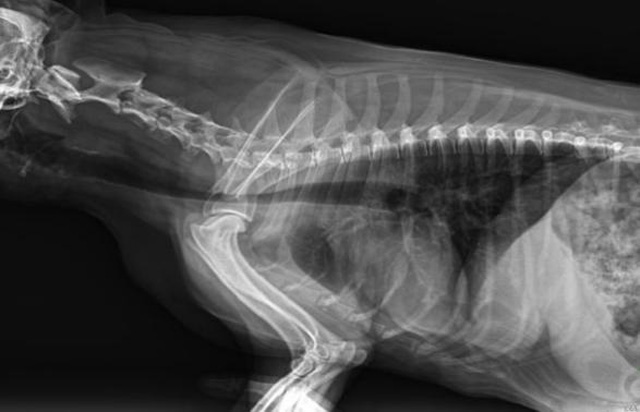

宠物DR是动物专用的数字化摄影系统,x线的穿透能力、低的辐射剂量,辐射剂量比X光低:荧光作用和感光作用,可以穿透动物身体的结构显示成像,动物的各个部位成像辅助兽医诊疗。宠物DR采集时间10ms以下,成像时间仅为3秒,从检查到出诊断报告大约5—10分钟。较高的空间分辨力和低噪声率,可获得高清晰图像。 DR成像数字化处理的特点可进行后处理。提高了病灶的检出率,这样大大提高检查的准确率提高诊断准确率避免漏诊误诊等情况。